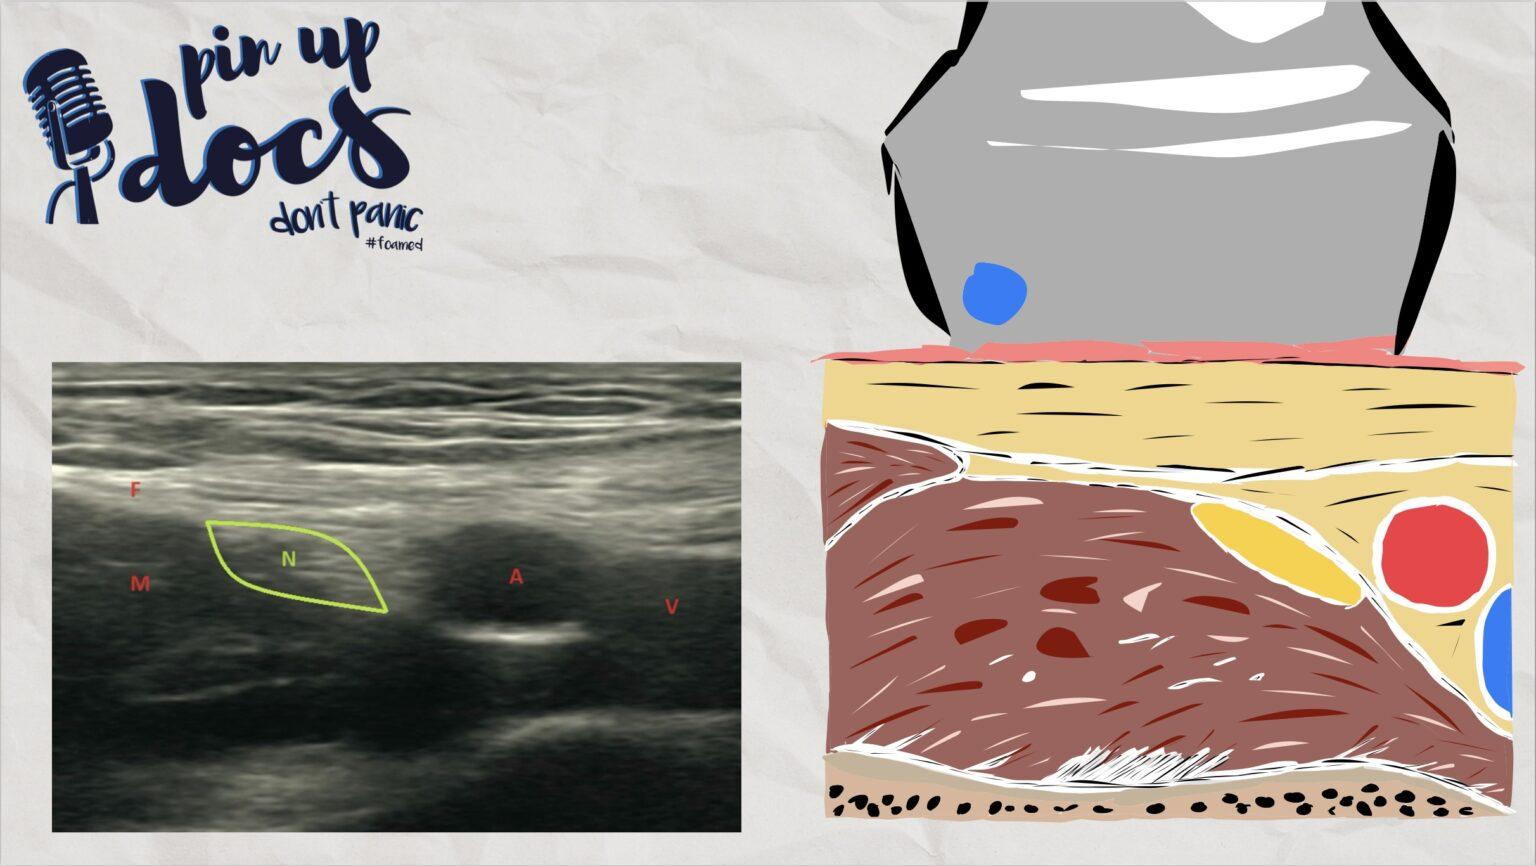

Sonotanatomie

- N: N. femoralis

- A: A. femoralis

- V: V. femoralis

- M: M. iliopsoas

- F: Fascia iliaca

Zum Identifizieren der Zielstruktur sollte man sich an der Lage der Femoralgefäße orientieren. Lateral hiervon verläuft der N. femoralis in der Leiste. Auch wenn er nicht immer einfach von dem umgebenden Bindegewebe abzugrenzen ist, stellt er sich in der Regel als dreieckige oder bohnenförmige Struktur dar. Die Punktion erfolgt von lateral in In-Plane-Technik, und beim Vorschieben der Nadel lassen sich zwei Faszienclicks spüren. Die Nadel wird zuerst, unter ständiger Visualisierung der Nadelspitze in Richtung des lateralen Nervenrandes, vorgeschoben. Nach dem zweiten Faszienclick und bei sicherer Visualisierung der Nadelspitze marginal unterhalb des Nerven kann eine Probeinjektion gemäß Standard erfolgen. Nach Lagebestätigung erfolgt die Gabe von bis zu 10 ml Lokalanästhetikum, wobei ein Auftreiben des Nerven zu sehen ist. Anschließend wird die Nadel oberhalb des Nerven geführt. Sodann erfolgt erneut eine Gabe von bis zu 10 ml Lokalanästhetikum.